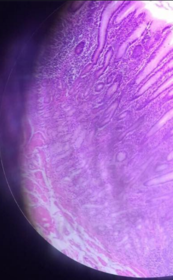

Duodenum HE